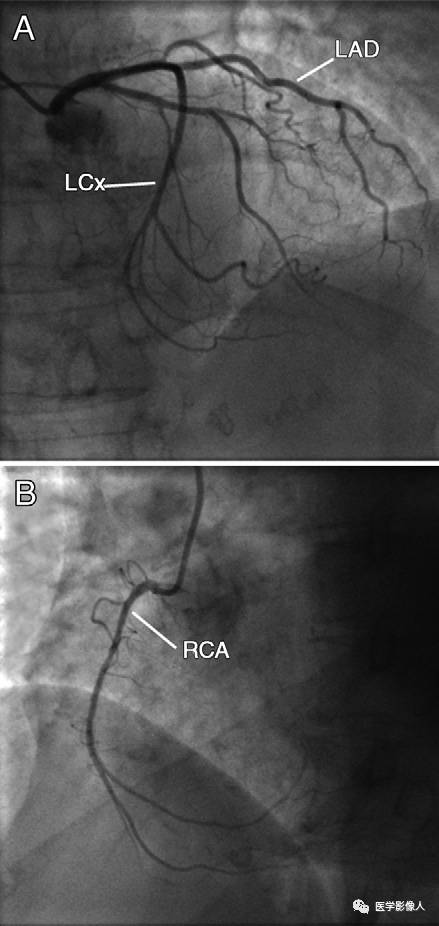

患者,69岁老年女性,有腹膜后纤维化病史,因心脏方面症状进行了心脏影像检查。

DSA